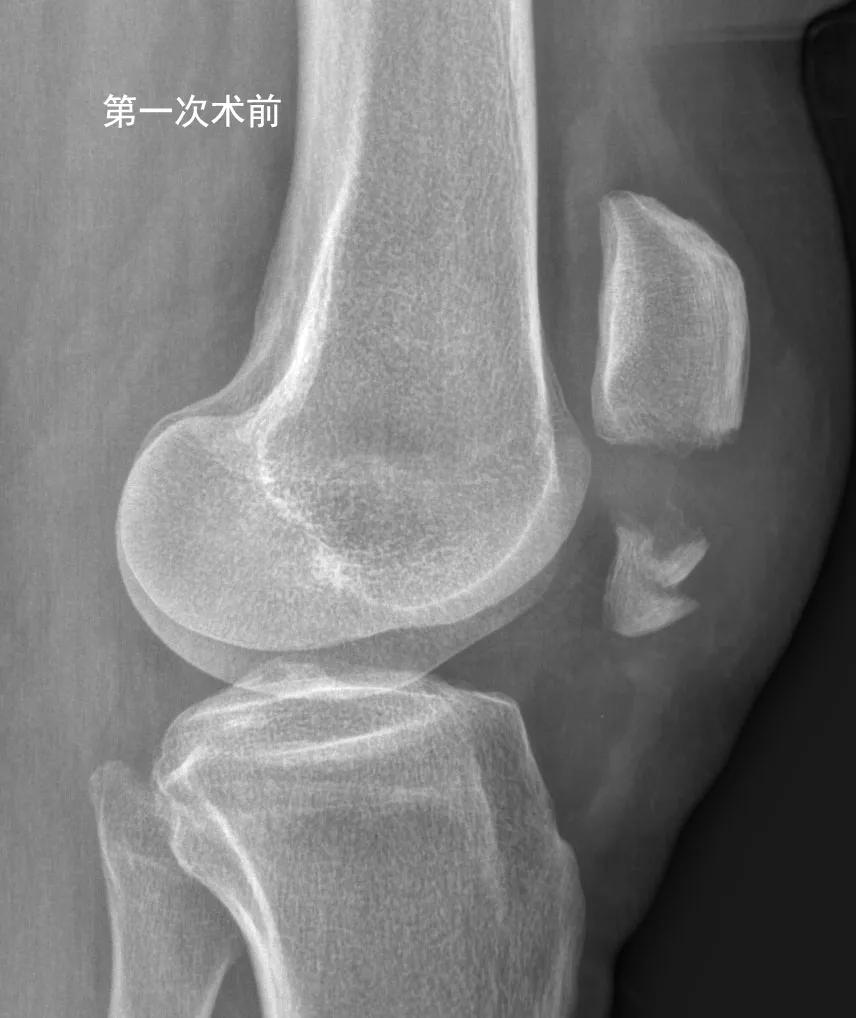

62岁洪女士,一个月前上台阶时摔倒,造成左侧髌骨下极骨折(如下图)。

为了避免膝关节术后粘连,洪女士按照康复师的指导,术后即在关节不疼痛的范围活动膝关节,术后2周拆线后加强膝关节的屈伸练习。为了获得良好的膝关节功能,洪女士咬牙克服康复练习的疼痛,没想到练习2周后膝关节肿痛越来越重。体疗师也感到奇怪,建议洪女士拍个片子看看,果然发现钢丝克氏针松脱了,髌骨下极骨折又分开了(如下图)。